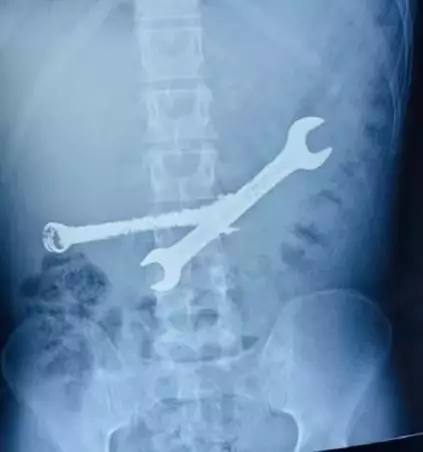

男子腹痛求診照X光 揭胃內藏多件硬物

男子腹痛就醫揭胃部藏異物,手術取出2把扳手7支牙刷。X平台圖片@ETV Bharat Rajasthan Team

日前,印度拉賈斯坦邦齋浦爾市一名26歲男子因腹部劇烈疼痛前往齋浦爾的SR卡拉紀念醫院求診。他向醫生表示腹痛已持續一段時間,院方隨即安排 X 光及腹部超聲波檢查,結果驚訝發現他的胃部存在多個形狀異常且質地堅硬的異物,即使是經驗豐富的醫生也感到難以置信。

院方一名資深胃腸外科醫生指出,患者的情況相當危急,之後進行的內視鏡檢查顯示,多件尖銳異物已深入胃壁,隨時可能引發穿孔或大量出血,無法以內視鏡方式取出。醫療團隊經評估後,隨即安排開腹手術,最終成功從患者胃中取出2把鐵扳手及7支牙刷。醫療團隊對此大感震驚,形容患者胃部猶如「垃圾桶」。所幸手術過程順利,成功挽回患者性命。